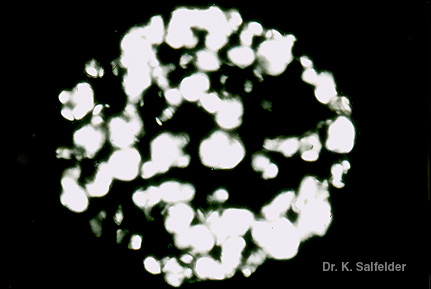

Abb. 11,12: Kokzidioidomykose

Dieselbe Sphaerule wie in Abb. 11,12 im polarisierten Licht. HE-Faerbung. In diesem Fall war das Gewebe vor der Faerbung nicht vollstaendig entparaffiniert worden